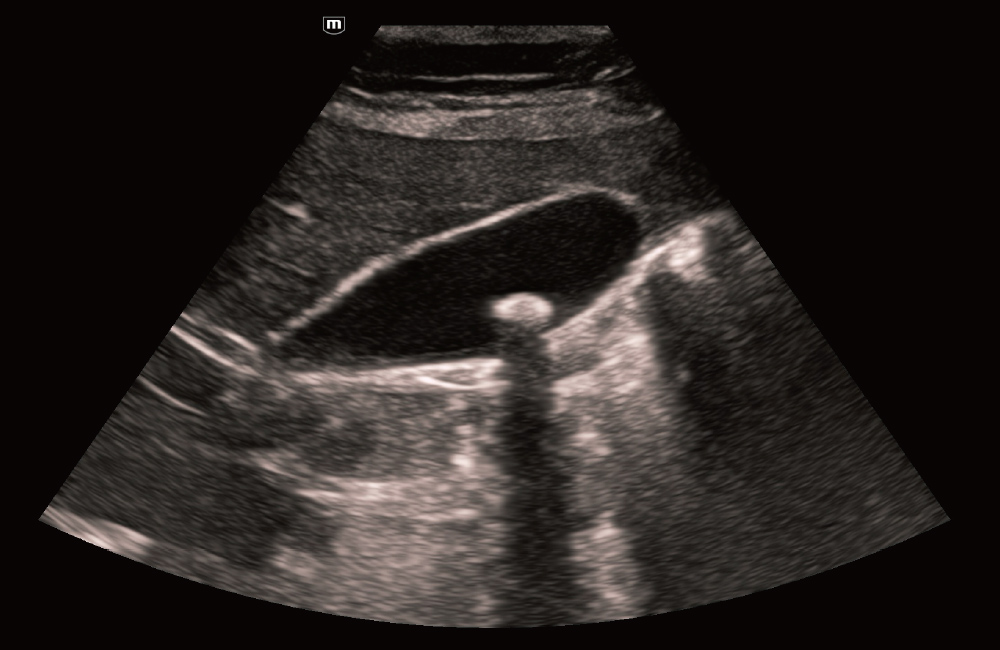

Galblaas met iTouch+